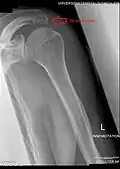

Radiograph of the shoulder showing an os acromiale

Os acromiale

The acromion has four ossification centers called (from tip to base) pre-acromion, meso-acromion, meta-acromion, and basi-acromion. In most cases, the first three fuse at 15–18 years, whereas the base part fuses to the scapular spine at 12 years. However, in between 1% and 15% of cases, this osseous union fails and the acromion remains separate as an accessory bone. This condition is referred to as os acromiale, but rarely causes pain. Earlier estimates of its prevalence were as low as 1.4%, and this higher estimate was made by Sammarco in the year 2000, based on radiographic and anatomical studies.[6][7]

Although historically regarded as an incidental finding, the os acromiale may occasionally produce symptoms from subacromial impingement or instability at the site of non-union.[9] In people with symptoms of os acromiale, dynamic ultrasound sometimes shows hypermobility in the area during shoulder movement, or graded compression with the probe.[10]